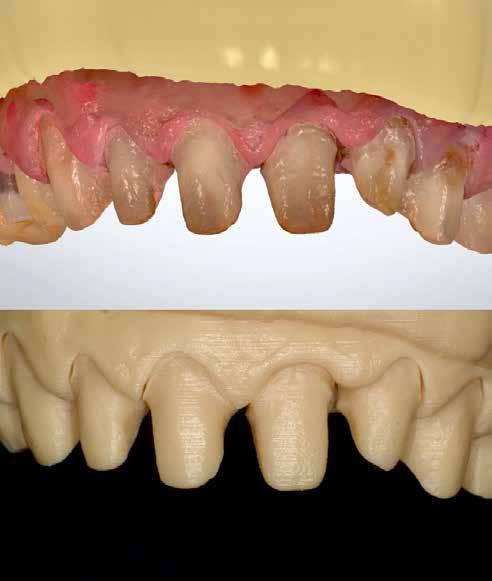

A cikkben egy fiatal nő kezelésének interdiszciplináris megközelítését foglaltuk össze, aki fogászati állapota miatt hoszszú ideje szenvedett fizikálisan és pszichésen is (1. ábra)

Amikor a 25 éves Andrea először konzultált a rendelővel, már több éve küszködött súlyos panaszokkal. Állapota két különböző betegségnek köszönhető, melyek egyrészt önmagukban, másrészt egymással kölcsönhatásban is súlyos következményekkel jártak. A fiatal nő veleszületett genetikai elváltozásban szenved, melynek tünete többek között a gyenge zománcfejlődés. Továbbá a beteget fibromyalgiával is diagnosztizálták, mely krónikus fájdalom rendellenesség, ami komoly tünetegyüttessel járó pszichés szorongás. A betegség egyik következménye az volt, hogy a páciens az elmúlt években átlagosan napi három-négyszer hányt. Az ebből fakadó savas erózió a már amúgy is veszélyben lévő fogazatot tovább roncsolta (2. ábra)

1. a–c ábrák: Kiindulási helyzet: fiatal páciens komoly fizikai és pszichés szenvedéssel.